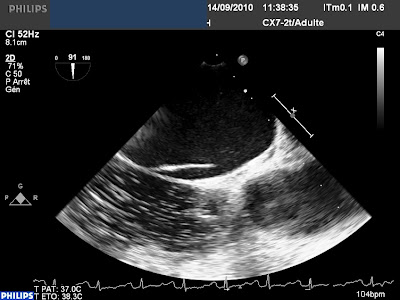

Ici l’association d’une petite Communication Inter Auriculaire de type ostium secundum

Et d’un FOP avec une épreuve de contraste faiblement positive :